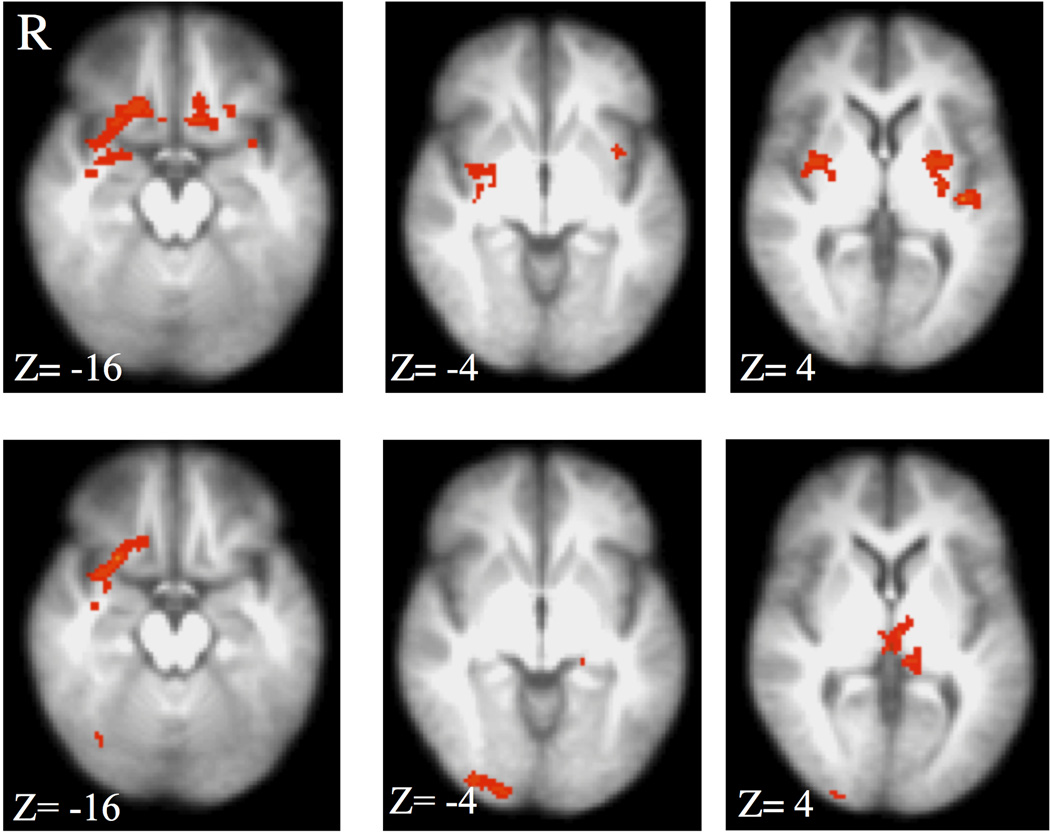

A significant interaction was observed between CAI and group on the high- vs. low-threat BOLD amplitude in the right amygdala, bilateral posterior putamen, left medial OFC, right medial OFC extending into the lateral OFC, right middle insula and left posterior insula (Table 2 and Fig. 1, upper panel). Within-group correlations revealed that the interaction was primarily driven by a negative relationship between CAI and BOLD amplitude in the alcohol-dependent subjects (right amygdala, bilateral posterior putamen, and insular regions; Table 2 and Fig. 2, upper panel). The only significant relationships in the control group were positive correlations between total CAI and the BOLD response in the OFC (Table 2; Fig. 2, lower panel). There were no significant positive relationships between CAI and BOLD high- vs. low-threat responses in the alcohol-dependent individuals or negative relationships in the control participants. Since our population included right-handed, ambidextrous, and left-handed participants, the interaction analysis was conducted using only right-handed subjects (12 in each group). Visual inspection of this analysis revealed nearly identical findings to Fig. 1.

Figure 1.

Top panel: Interaction between group (alcohol-dependence and control) and Childhood Adversity Interview (CAI) on the BOLD response to high- vs. low-threat CS. A significant interaction (z=2.58, p<0.05, corrected) was observed in the bilateral posterior putamen, right amygdala and middle insula, right and left OFC, and posterior insula. Bottom panel: Interaction between group and CAI subdomain Separation/Loss. Overlapping areas with the total CAI score interaction were limited to the right OFC. R= right, z = MNI transverse coordinate.

To determine whether these findings were particular to domains of the CAI, similar linear models, assessing group and CAI interactions, were applied to each of the domains separately (Fig. 1, lower panel). Only the Separation/Loss domain of the CAI revealed a significant interaction with group. The Separation/Loss domain-specific analysis overlapped with the analysis of total CAI only in the right OFC (Fig. 1, two left panels).